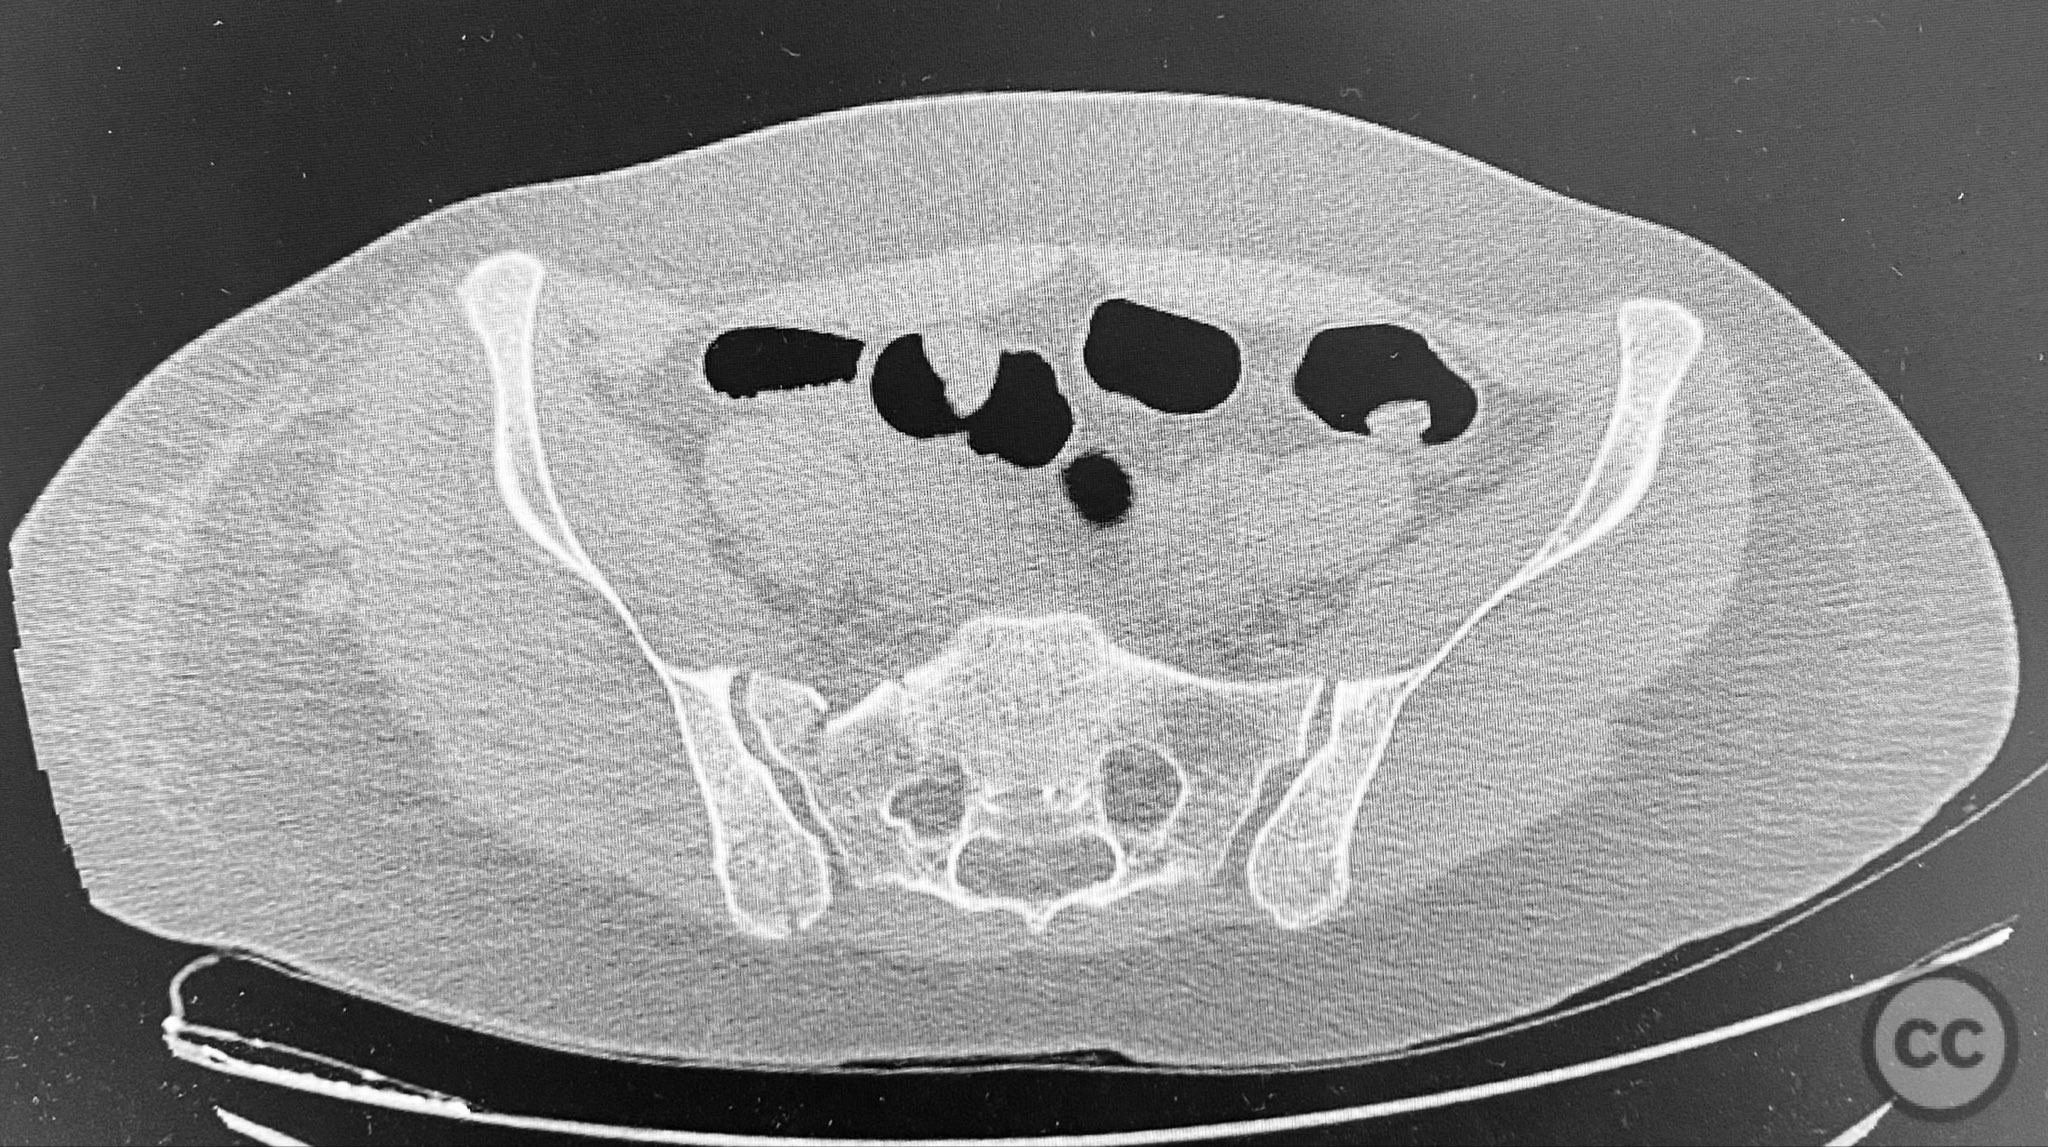

Clinical and radiological findings:  A middle-aged patient involved in a motor vehicle collision presented initially with a closed ankle fracture-dislocation and minimal pelvic complaints. Following closed reduction and splinting of the ankle, the patient developed severe pelvic pain (9/10) with any attempted movement. Neurological and vascular examination was not specified. Computed tomography demonstrated minimally displaced fractures of the posterior ilium, sacral ala, and bilateral pubic rami. AP CT surface renderings revealed subtle but clinically significant displacement and deformity of the pelvic ring, which was difficult to appreciate on standard axial images.

Anatomical surgical approach:  Percutaneous approach: Small stab incisions were made over the crista iliaca and sacral entry points as determined by preoperative imaging. Under fluoroscopic guidance, guidewires were advanced across the sacroiliac joint and sacral ala as indicated. Cannulated screws were inserted percutaneously to stabilize the unstable posterior pelvic ring and rami fractures.

Intraoperative assessment confirmed instability at the posterior pelvic ring with manual stress testing under fluoroscopy. Reduction was achieved with gentle manipulation and maintained during percutaneous screw insertion. The use of intraoperative inlet and outlet views was critical for accurate screw placement and confirmation of reduction. The minimally invasive technique minimized additional soft tissue trauma in this polytrauma patient.